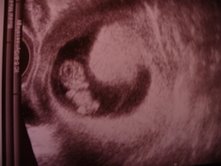

Gomba, szépséges pocód van! Nagyon izgi! Drukkolok, hogy problémamentes szülésed legyen!

Heim Pál durvaaaa!!!!! Kis hősök ezek a gyerekek, hogy bírják. Mi december 14-én megyünk UH-ra. Remélem, az időpont az időpont, és nem éjszakázunk ott, mert du. kell menni.